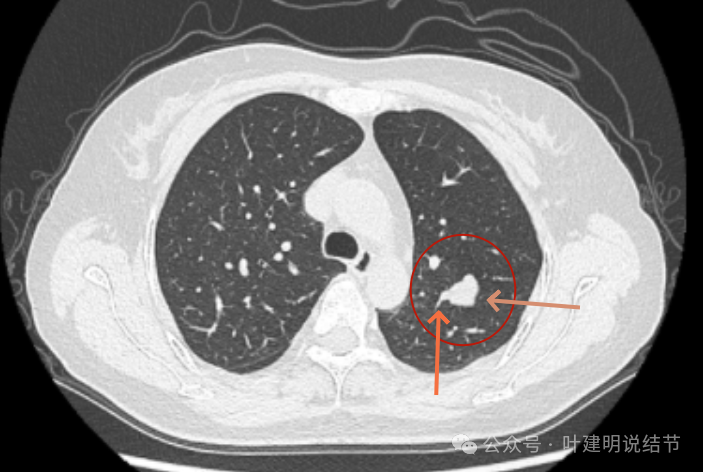

2020年5月,病灶仍是边缘非常光滑,局部表面似有凹陷。

2021年9月,病灶相仿,但与邻近血管的距离似乎较最初的更靠近一点。